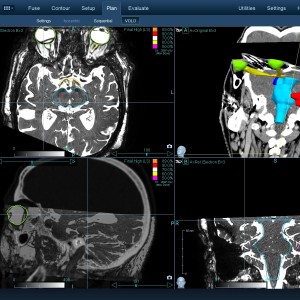

Στις παρακάτω φωτογραφίες θα δείτε παραδείγματα πλάνων θεραπείας καρκινικών όγκων με CyberKnife. Παρατηρήστε πόσο κοντά στους υγιείς ιστούς βρίσκονται οι καρκινικοί όγκοι που χρειάζεται να ακτινοβοληθούν. Μόνο με το CyberKnife και το προσωπικό πλάνο θεραπείας, μπορούν να ακτινοβοληθούν οι όγκοι χωρίς να πληγούν οι παρακείμενοι υγιείς ιστοί.

Μόνο με το CyberKnife και την κατάλληλη σχεδίαση της θεραπείας από έμπειρο νευροχειρουργό, μπορεί να ακτινοβοληθούν οι όγκοι χωρίς να επηρεαστούν από την ακτινοβολία οι υγιείς ιστοί. Αυτό εξασφαλίζει τη μέγιστη δυνατή απόδοση της ακτινοχειρουργικής θεραπείας των όγκων.

Ο νευροχειρουργός Λέκας Λεωνίδας έχει τη μεγαλύτερη εμπειρία στην Ελλάδα στο σχεδιασμό θεραπειών στερεοτακτικής ακτινοχειρουργικής όγκων του εγκεφάλου και του νευρικού συστήματος σε CyberKnife. Ο σχεδιασμός του πλάνου θεραπείας προϋποθέτει άριστη γνώση της ανατομίας και της απεικόνισης του κεντρικού νευρικού συστήματος έτσι ώστε να επιτευχθεί το βέλτιστο θεραπευτικό αποτέλεσμα με τη μέγιστη δυνατή προστασία των ευαίσθητων δομών.

Με κόκκινο χρώμα περιγράφεται η περιοχή του όγκου.

Με μπλε, κίτρινο και πράσινο χρώμα περιγράφονται οι υγιείς ιστοί που δεν πρέπει να ακτινοβοληθούν.

Παρατηρήστε πόσο κοντά βρίσκεται ο όγκος με τους υγιείς ιστούς.